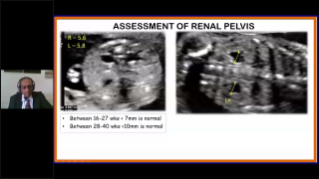

L'optimisation des flux de travail en gynÊcologie et obstÊtrique est indispensable pour traiter les volumes importants de patientes se prÊsentant pour des dÊpistages. Par exemple, les malformations du système nerveux central (SNC) font partie des anomalies congÊnitales les plus frÊquentes. Compte tenu des diffÊrentes conditions dans lesquelles sont rÊalisÊes les Êchographies, par exemple lorsque le f?tus est mal positionnÊ, il est particulièrement difficile de visualiser le plan transcÊrÊbelleux sur les Êchographies 2D. L'automatisation de la dÊtection et de la prise de mesures peut donc grandement amÊliorer l'efficacitÊ de l'imagerie.